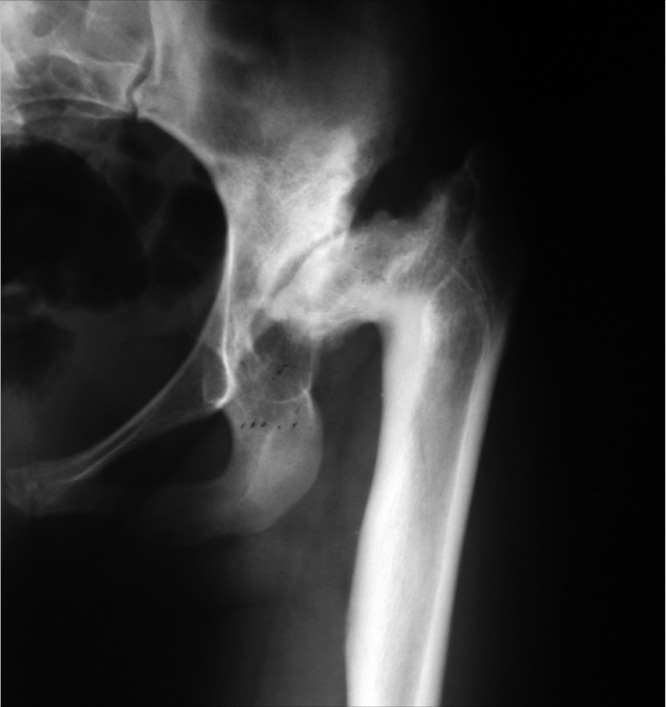

В 2001 г. по поводу левостороннего диспластического коксартроза в условиях 2-го отделения ЦИТО выполнено первичное тотальное эндопротезирование левого тазобедренного сустава (рис. 3, 4).

Рис. 3. Рентгенограмма левого тазобедренного сустава на момент поступления в клинику для первичного эндопротезирования в 2001 г.

Рис. 4. Рентгенограмма левого тазобедренного сустава после первичного эндопротезирования в 2001 г.